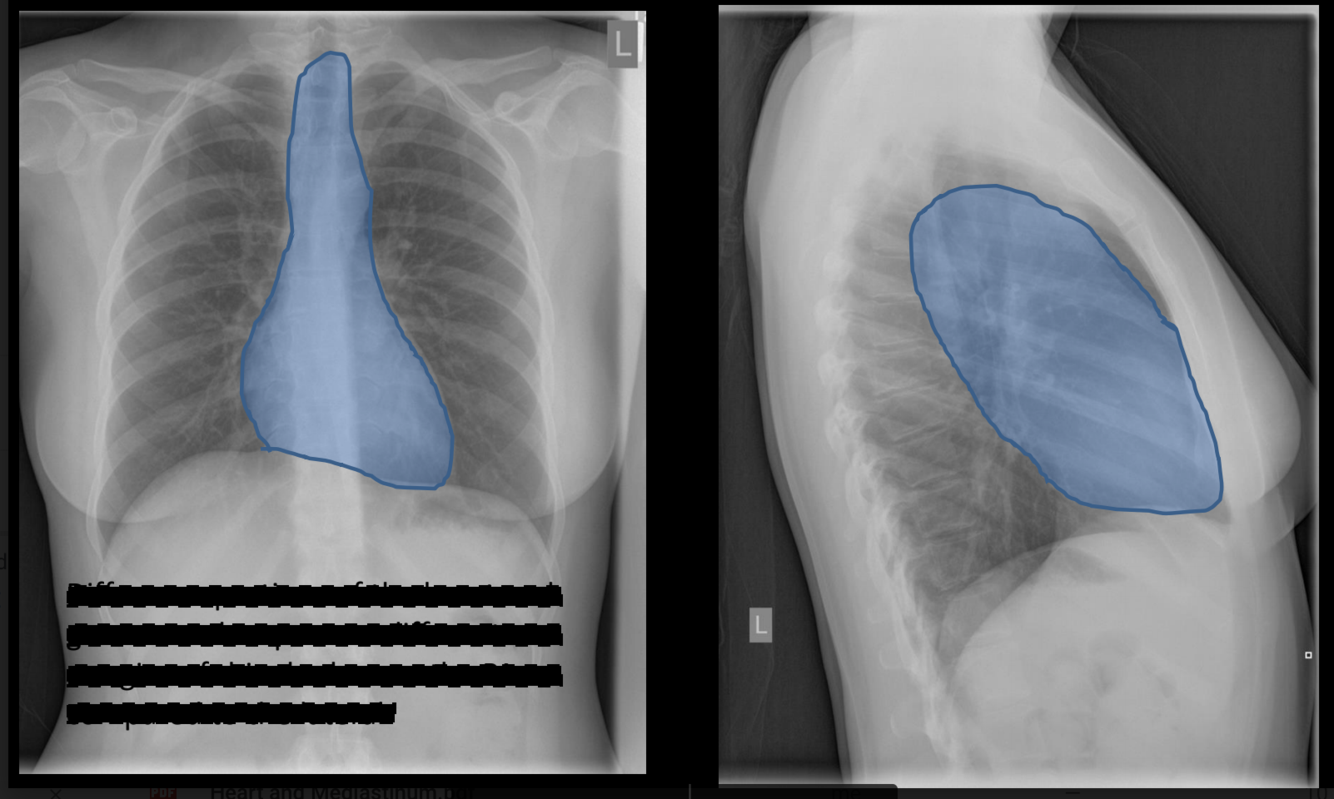

what is the blue outline?

mediastinal shadow